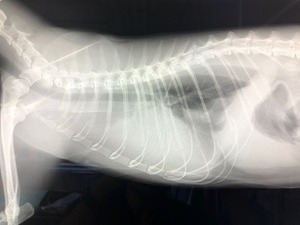

基本的に診断はレントゲンとエコー(胸水の採取)です。

これが膿胸症例のレントゲン写真です。

片方の肺が真っ白になって見えなくなってしまっています。

実際には肺はこの中に存在するのですが、大量に膿が貯留することで見えなくなってしまっているのですね。(レントゲンでは空気は黒く、液体はやや白く写ります)

これだけでは、胸水と鑑別ができませんので、次にエコーを用いて胸水の採取を行います。

そこで膿汁が採取されれば、『膿胸』と診断されるというわけです。

(肺炎や腫瘍の有無はまた別ですが…)